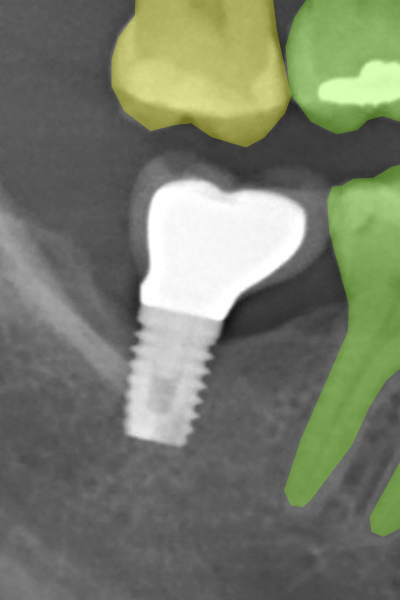

The O2PR data set includes 850 manually annotated images, from which 650 have their labels public, while the labels of other 200 images remain private for model assessments on the OdontoAI platform. We started from a former work from ours (Pinheiro et al., 2021), in which four students labeled a subset of 450 images from the UFBA-UESC Dental Image Data Set. In that work, the image selection was random but respected the original data set’s category proportions. The students were two dentistry undergraduates and two STEM graduates experienced in the research of tooth segmentation and numbering on panoramic radiographs. An experienced radiologist supervised the students’ work. Each student labeled about a fourth of the images using the COCO Annotator software and its polygon tool (Brooks, 2019). The annotators should click on the tooth borders precisely as possible to delineate the teeth’ outline, being expected crisper segmentations on sharp and well-focused images. On blurry images or regions, the students should picture the tooth contours based on their anatomical structure and label them accordingly, except when there was solid evidence for not doing so. some criteria were defined as to be the standards for the labeling procedure:

Implants should not be labeled;

Figure 3 displays corresponding label samples of the aforementioned criteria. We followed the same criteria to label 400 additional images (40 per radiograph category). These images compounded our test set for assessing the neural networks trained at each HITL iteration.

Refer to caption

(a) Implants.

Figure 3: Label samples of the employed criteria for annotating implants, prostheses, molar roots, restorations, and dental appliances. In general, the labels should be more refined on sharp and well-focused images, while in blurry images, the annotators should rely more on the tooth anatomical structures.